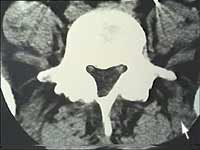

Hier das Bild einer Computertomographie. Der dreieckige Wirbelkanal, sollte sauber abgegrenzt sein.

Führen Sie Ihren Mauszeiger über das Bild um die mediolaterale Hernie zu sehen.

Die Grösse der Hernie ist jedoch für den Erfolg der Behandlung nicht immer so wichtig, sondern die Lage der Hernie ist oft entscheidend. Drückt eine kleine Hernie gerade beim Austritt aus dem knöchernen Nervenfenster auf den Spinalnerve, so kann dieser nicht ausweichen, und es sind ausgeprägte Lähmungen zu erwarten. Auf der anderen Seite können breitbasige Protrusionen ohne grössere Auswirkungen bleiben.

Bild 1: kleine linkslaterale Hernie Bild 2: breitbasige Protrusion |

Bild 1: Normale CT. Bei den Hernien-ähnlichen Aufhellungen handelt es sich um die zwei abgehenden Spinalnerven.

Bild 2: Hier eine Hernie welche fast 1/3 des Wirbelkanals ausfüllt. Sie musste nicht operiert werden!